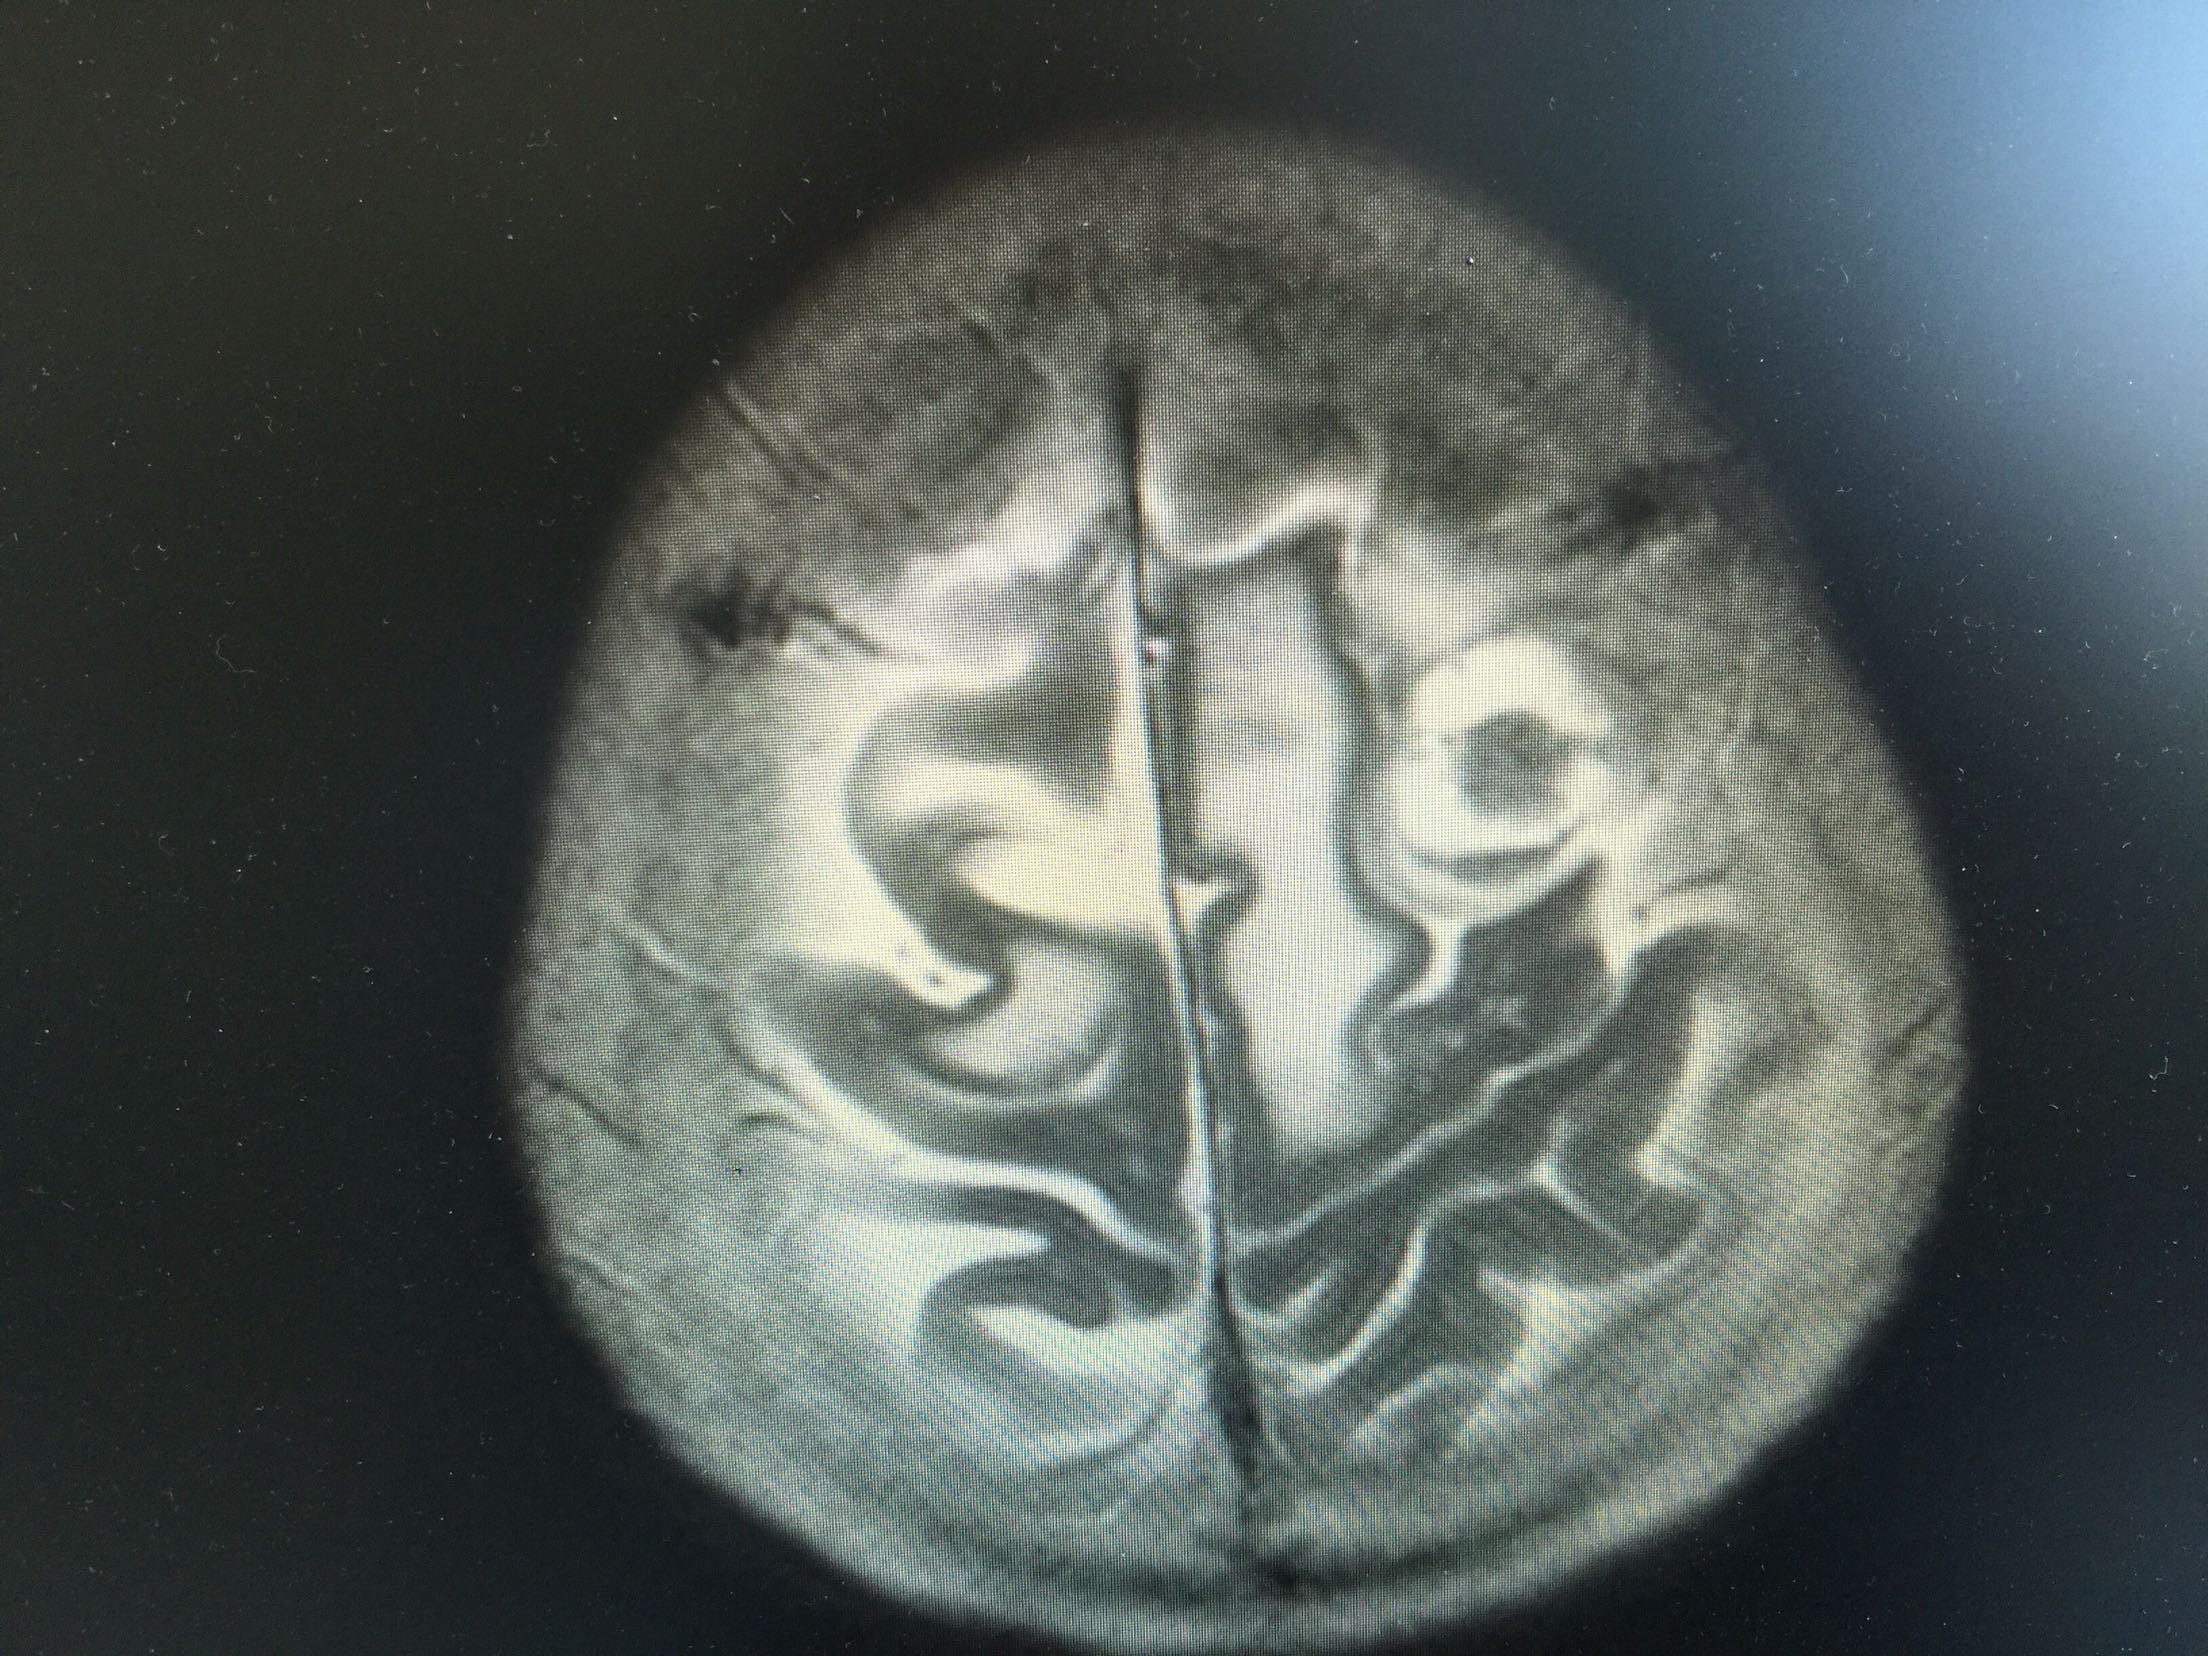

1.女,81岁,以“右侧肢体无力3天”入院。 2.现病史:3天前无诱因出现右侧肢体无力,右上肢抬举费力,右下肢步行拖拉,无抽搐,无意识障碍! 3.既往史:2016年肺穿刺活检,免疫组化为腺癌!已合并第五、六椎体转移、左肾上腺转移,行灌注介入治疗。

查体:血压:130/80mmHg,两肺呼吸音清,未闻及啰音,心率98次/分,律齐,未及杂音,双下肢无水肿。神经系统查体:意识清,双侧瞳孔等大正圆,直径约3.0mm,对光反射灵敏,无面舌瘫,右侧肢体肌力4级,腱反射减弱,Babinski征R+L-。

左肺腺癌 骨转移、双肺门及纵膈淋巴结转移、左肾上腺转移、脑转移! 治疗:对称、支持治疗!